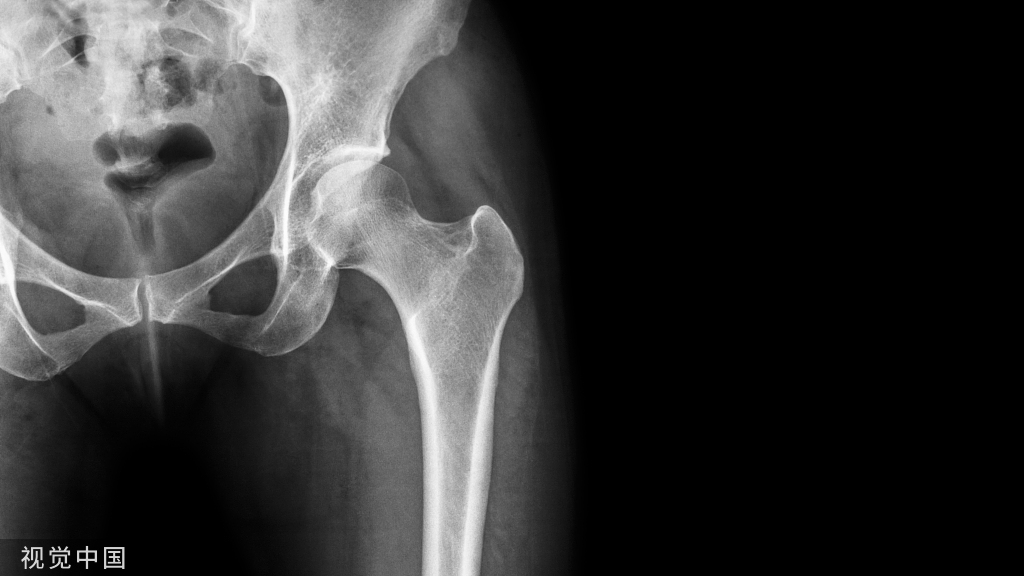

其他辅助检查:X 线照片显示肿物的软组织当中有分散钙化影。过一段时间,急性期的症状和体征消失后,肿物变小,钙化影也缩小,但密度增高。X 线片上可见柱状或不规则形态的团块状不同密度的骨化阴影,可与骨骼相连,也可完全游离。骨骼呈现失用性萎缩。